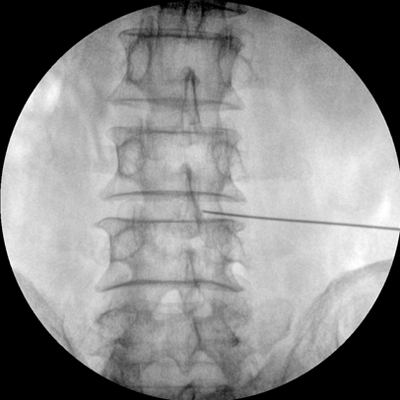

專業(yè)的圖像處理系統(tǒng),為您提供高分辨率、高灰階圖像。